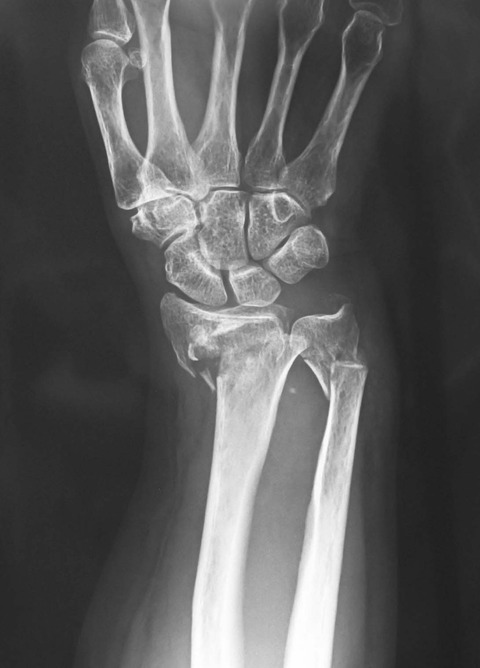

先日、橈尺骨遠位端骨折に対して骨折観血的手術を施行しました。下図のように、橈骨・尺骨とも非常に不安定性が強かったので、尺骨にも骨接合術を計画しました。